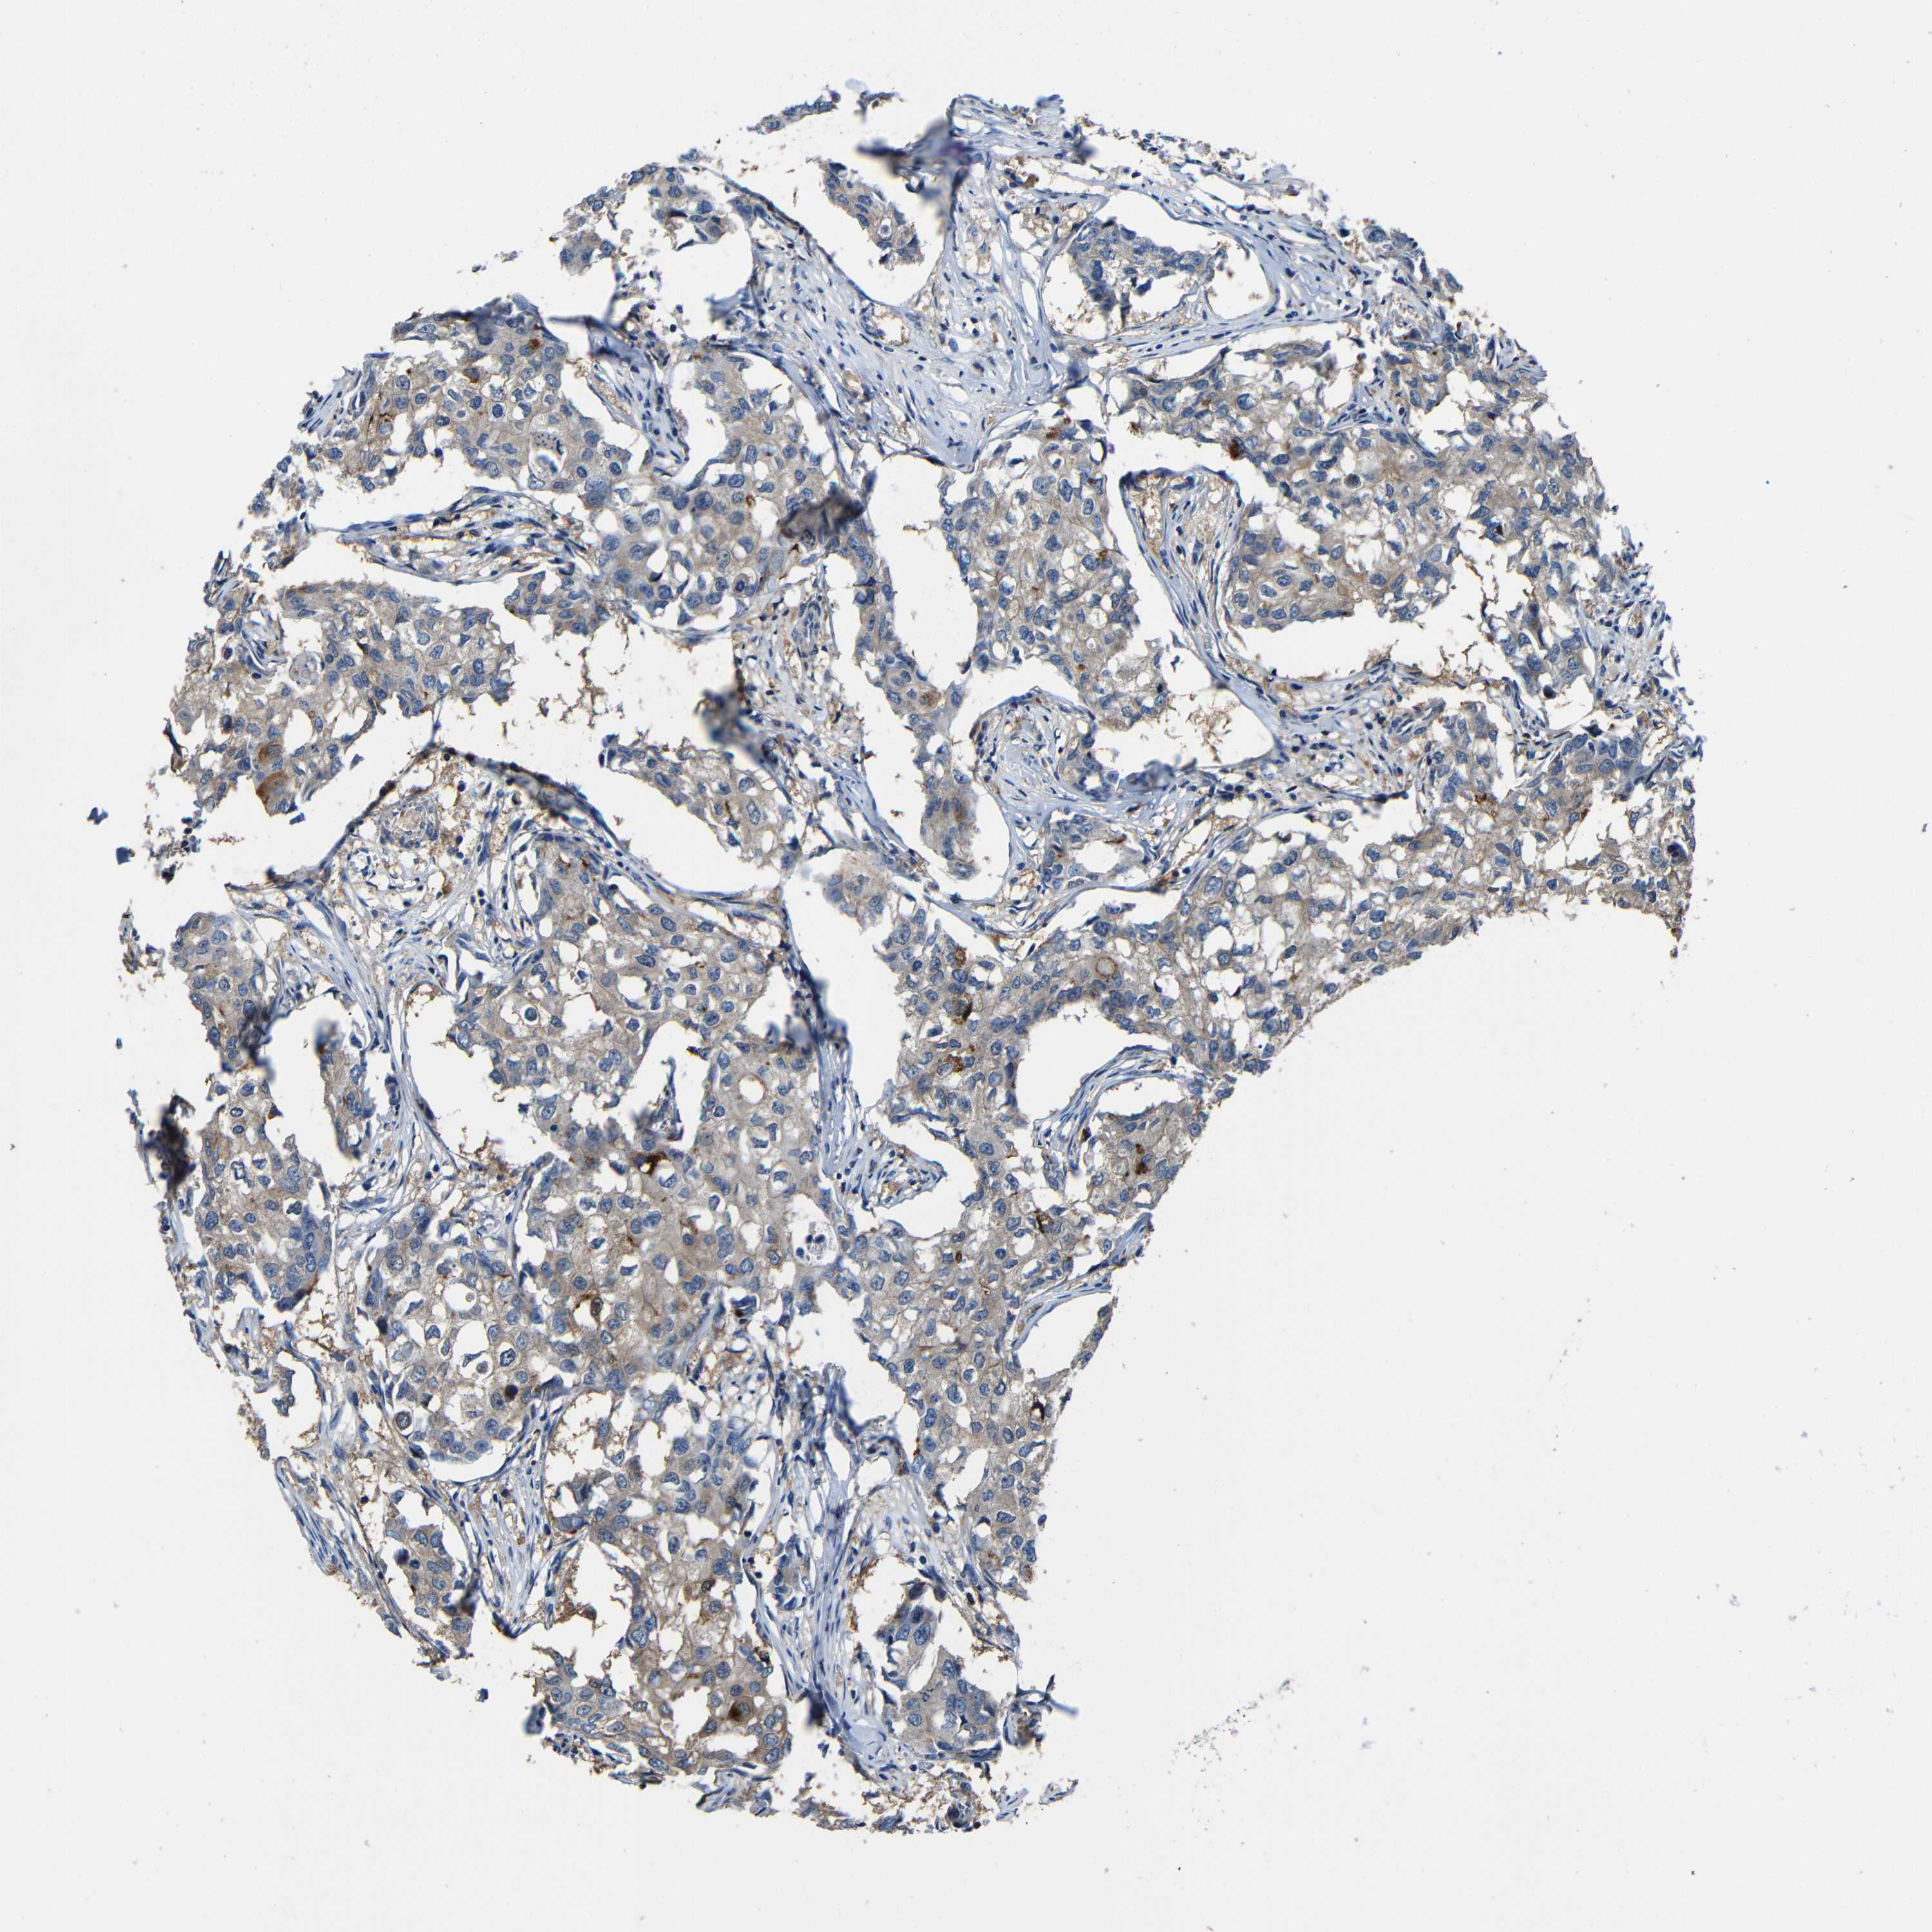

BRCA TCGA BRCA VALIDATION PROTEIN EXPRESSION

Breast cancer

Human cancer

Breast invasive carcinoma